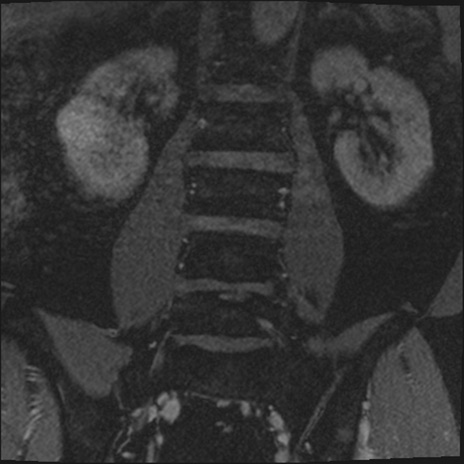

【整形】TIPS症例2 腰椎MRI 3D(冠状断像)

【症例】70歳代男性

【主訴】左下肢痛

【現病歴】2週間前くらいから腰痛、左下肢痛あり。左臀部から大腿、下腿外側のしびれが常時ある。歩行とともに同部位の痛みあり。

【身体所見】Lasegue70-/60+、Bragard-/±、PTR ±/±、ATR -/-、IP 5/5、TA 5/4、TS 5/5、EHL 右第1足趾なし/3、FHL 5/5、hypersthesia(-)、足背動脈触知良好

異常所見と診断は?